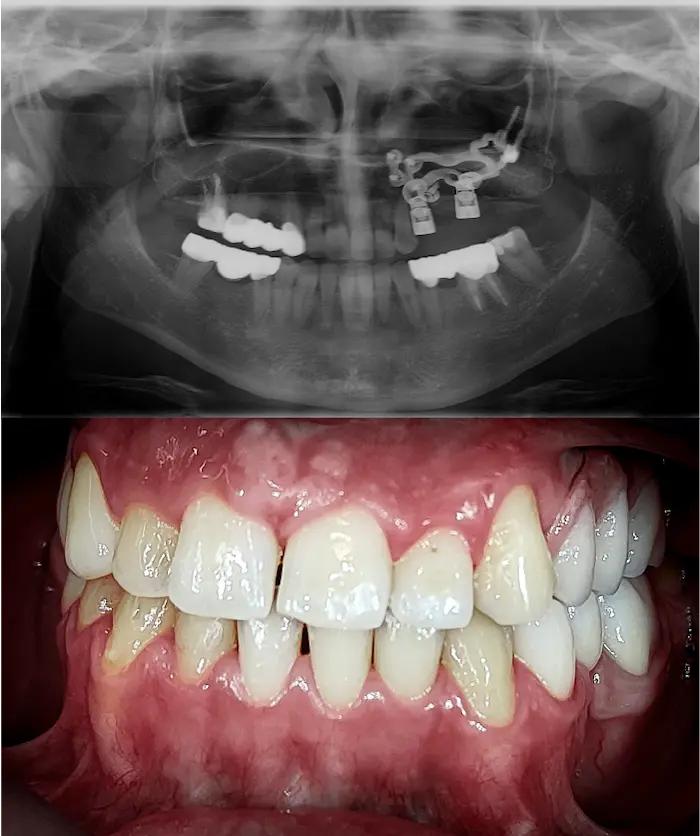

Quando manca anche solo uno di questi fattori, l’implantologia classica non è possibile. Ma gli impianti zigomatici e gli impianti sottoperiostei permettono di ottenere comunque denti fissi.

Se hai ricevuto un rifiuto, non è che “non si può fare”, è che servono competenze chirurgiche avanzate, disponibili in poche cliniche.

Durante la prima visita valutiamo se sei un candidato per impianti All-on, impianti zigomatici o impianti subperiostali.